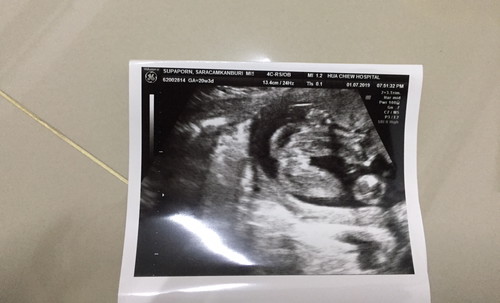

อัลตร้าซาวด์

แบบนี้คือเพศไหนรบกวนดูช่วยหน่อยค่ะ?

น่าจะผู้หญิงนะคะคุณแม่^^เหมือนเห็นกลีบค่ะ

ผู้ญิง แน่ๆนอนคะ😊

น่าจะผญ นะคะ

คิดว่า ญ ค่ะ